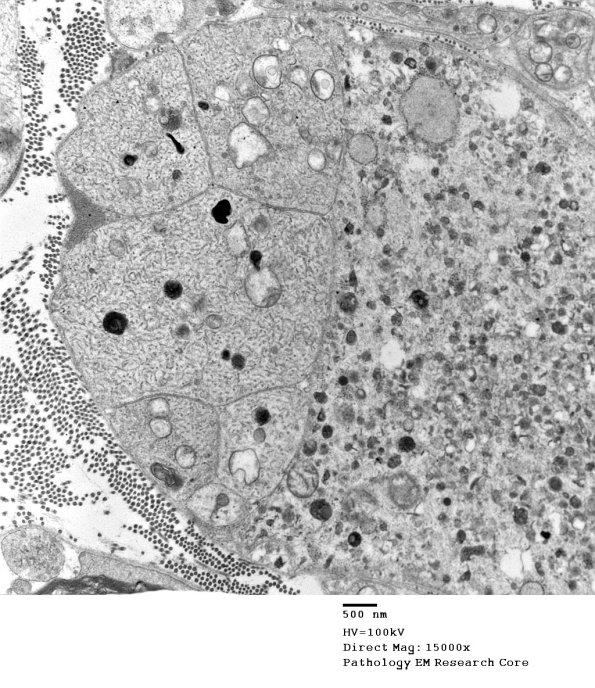

3B7A Axonal regeneration, SLE NP Vasculitis (Case 1)_042 - Copy

3B7A,B Higher magnification of image 3B7. (electron micrographs)